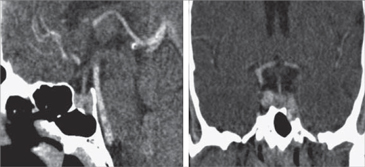

En la Prueba de Supresión con Glucosa se obtuvo a los 30 minutos 3,26 ng/ml, a los 60 minutos 2,1 ng/ml, a los 90 minutos 1,63 ng/ml y a los 120 minutos 1,32 ng/ml. También se realizó una TC de región Selar y un Ecocardiograma de control. En la TC no se observaron variaciones signifi cativas en relación al tamaño de la lesión (Figura 3). En el Ecocardiograma se apreció importante mejoría (Tabla 1), acercándose a parámetros normales; con un ventrículo izquierdo de 61/42 mm, Atrio izquierdo 33 mm, Función Eyectiva de 56%, Índice de Masa 175 g/m2 e Insuficiencia Mitral leve.

Figura 3. TAC de silla turca post tratamiento.Tabla 1. Ecocardiograma pre y post tratamiento